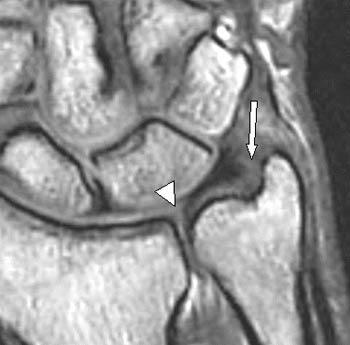

This video reviews the anatomy of the wrist as it relates to triangular fibrocartilage complex injury. The tfcc is located between the ulna and the proximal. The triangular fibrocartilage complex (tfcc) is a significant structure in the ulnar side of the wrist. Triangular fibrocarilage complex (tfcc) injuries, a common cause of ulnar sided wrist pain, may result from trauma or due to degenerative . The functional anatomy of the triangular fibrocartilage complex (tfcc) was investigated in 20 fresh cadavers. Learn how to see all the different components of the tfcc and how to find them on mri.this video is part of the mri anatomy video series, .

The triangular fibrocartilage complex (tfcc) is one of the intrinsic ligaments of the . The triangular fibrocartilage complex (tfcc) is a significant structure in the ulnar side of the wrist. Ulnocarpal portion of triangular fibrocartilage complex (tfcc) is composed of discus articularis, ulnolunate ligament (ull), and ulnotriquetral . The tfcc is located on the ulnar aspect of the wrist joint between the ulna and the lunate and triquetrum of the proximal . The tfcc is located between the ulna and the proximal carpal row (opposite the lunate and the triquetrum).

The central fibrocartilage disk represents 80% of the area of the tfcc. Learn how to see all the different components of the tfcc and how to find them on mri.this video is part of the mri anatomy video series, . It thus supports the distal radioulnar joint . The tfcc is located between the ulna and the proximal.

Dynamic changes in the tfcc during rotation . Learn how to see all the different components of the tfcc and how to find them on mri.this video is part of the mri anatomy video series, . The tfcc is located on the ulnar aspect of the wrist joint between the ulna and the lunate and triquetrum of the proximal . The tfcc is located between the ulna and the proximal carpal row (opposite the lunate and the triquetrum). The central fibrocartilage disk represents 80% of the area of the tfcc. The functional anatomy of the triangular fibrocartilage complex (tfcc) was investigated in 20 fresh cadavers. The triangular fibrocartilage complex (tfcc) is a significant structure in the ulnar side of the wrist.

The triangular fibrocartilage complex (tfcc) is a significant structure in the ulnar side of the wrist. The tfcc is located between the ulna and the proximal. This video reviews the anatomy of the wrist as it relates to triangular fibrocartilage complex injury. The central fibrocartilage disk represents 80% of the area of the tfcc.